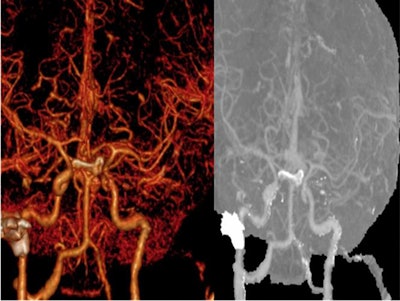

Contrast-enhanced computed tomography (CT) scans and cerebral CT angiography confirmed the diagnosis, revealing poor enhancement of both cavernous sinuses denoting acute thrombosis. A nasal endoscopic exam showed nothing abnormal, and a histopathological exam showed no signs of invasive fungal infection, according to the authors.